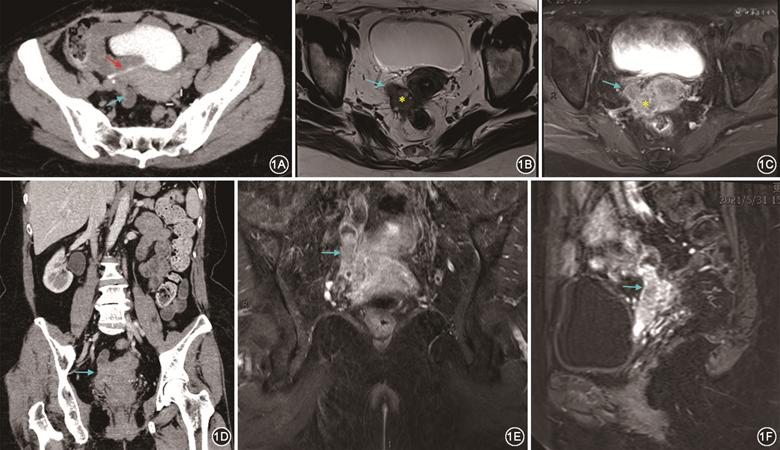

专科检查:双肾区无隆起,无压痛及叩痛。妇科检查:子宫萎缩,右侧宫旁触及一大小约4 cm肿物,质硬,活动差。泌尿外科联系本科会诊后转入本科。术前检查血清癌抗原125(CA125)水平为50 kU/L,人附睾分泌蛋白4(HE4)水平为96 pmol/L。盆腔彩超:盆腔见管状肿块,大小为3.7 cm×1.3 cm×1.1 cm,边界清,似沿输尿管走行,见稍丰富血流信号,提示:右侧输尿管癌?磁共振成像(MRI)检查:膀胱右后方、子宫右侧见团片状、柱状异常信号,与膀胱相连,大小为3.6 cm×2.7 cm×5.8 cm,考虑:肿瘤性病变,右侧输尿管残端来源?右侧附件来源?见图1。CT检查:右侧肾盂呈壶腹型扩张,右侧输尿管下段呈细线样开口于膀胱顶后壁,膀胱后方见一管状实性团块影,边界不清,与膀胱后壁、子宫颈、直肠外壁粘连,范围为2.4 cm×2.4 cm。提示:右侧输尿管下段开口异常,考虑术后改变;膀胱后方软组织肿块,考虑残余输尿管并发肿瘤性病变。正电子发射体层摄影(PET)-CT检查:子宫右侧占位性病变,大小约3 cm,与子宫及直肠粘连,与膀胱后壁关系密切,右侧输尿管下段显示不清,考虑恶性肿瘤,输尿管来源?右侧肾盂、右侧输尿管上段扩张、积水。于2021年6月11日行剖腹探查术,术中见:子宫、卵巢萎缩,膀胱盆底粘连严重,右侧输尿管再植处及原输尿管口处突起,膀胱壁外右后侧壁触及一大小约7 cm×3 cm条索形质硬组织,再植输尿管下端及输尿管残端被包裹其中。根据术中情况决定继续行经腹子宫全切除+双侧附件切除+阑尾切除+右侧盆腔淋巴清扫+肠粘连松解+右侧输尿管残端切除+右侧输尿管膀胱再植+膀胱肌瓣代输尿管成形+膀胱外肿物切除+右侧输尿管支架置入术。术后常规病理检查及免疫组化法检测提示:右侧输尿管中分化子宫内膜样癌,癌细胞浸润输尿管固有肌层及外膜,ER、PR(+),见图2;子宫腺肌病,子宫平滑肌瘤,萎缩性子宫内膜;子宫后壁浆膜面、深肌层见癌细胞累及,双侧附件未见癌细胞累及;膀胱外肿物见转移性和浸润性高分化子宫内膜样癌,见脉管内癌栓,ER 85%(+),PR 8%(+)。术后诊断:右侧输尿管中分化子宫内膜样癌,术后患者接受了多西他赛+洛铂方案的联合化疗,21 d为1个疗程,共6个疗程,化疗后随访至今无复发迹象。